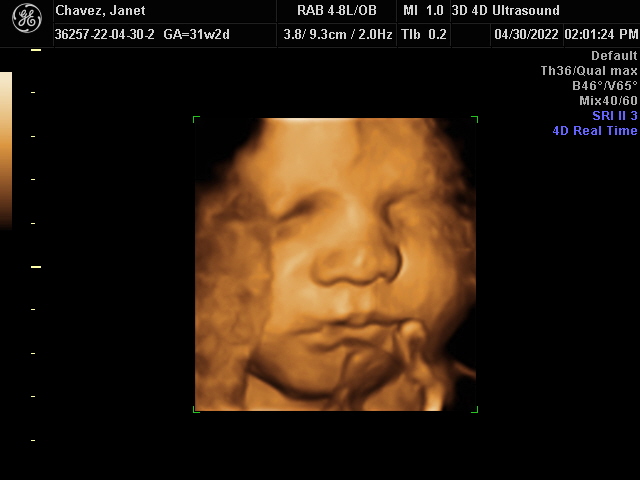

Our Gallery

Explore beautiful moments captured during our 3D and 4D sessions.